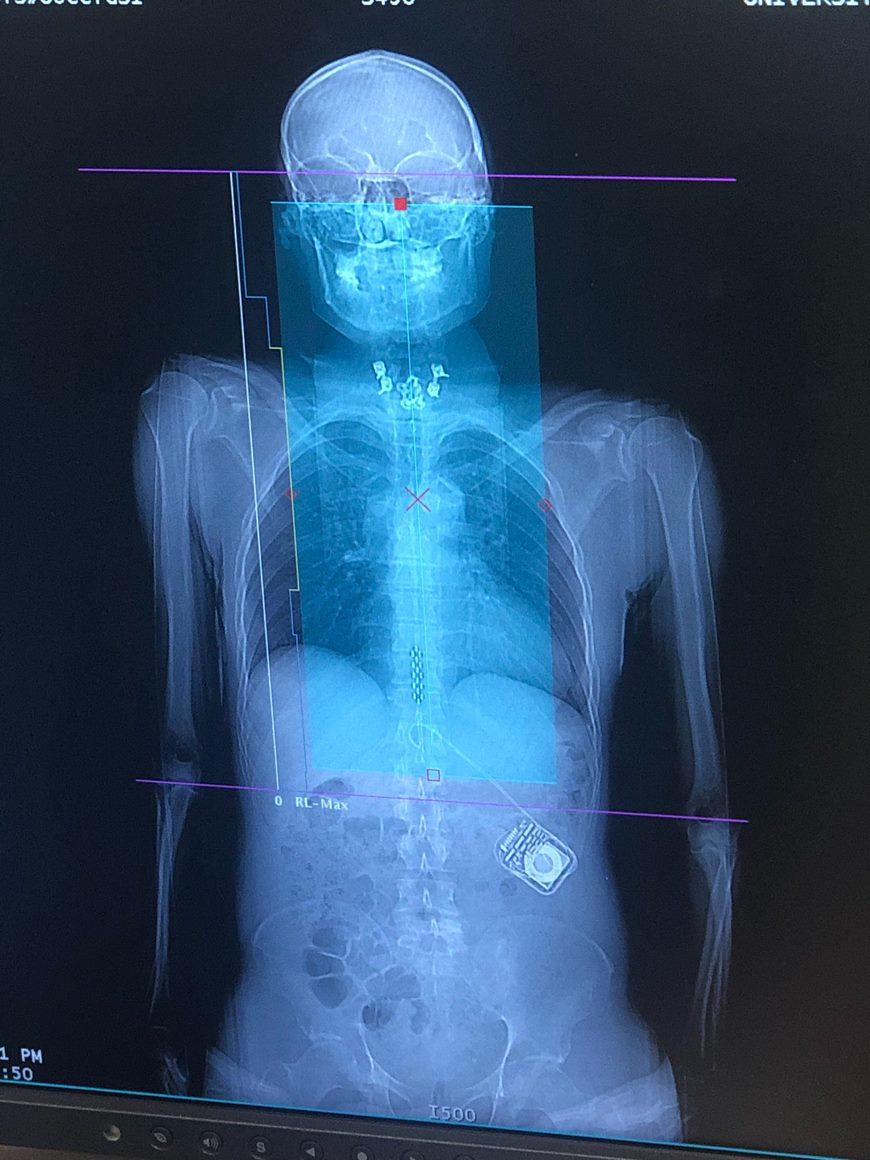

Clinical tools used in the lab include vascular and cardiac ultrasound, beat-by-beat blood pressure, cardiac, cerebral and spinal cord MRI, orthostatic stress testing, exercise stress testing, functional electrical stimulation, passive cycling, arterial blood gas reactivity testing (RespirAct Gen IV), both surgically implanted and non-invasive neurostimulation modalities, eye tracking, muscle sympathetic nervous system recordings, etc. Preclinical tools include various tissue clearing methods (CLARITY, uDISCO) arterial cannulation, nerve recordings, spinal cord transection/contusion, and a variety of genetic strains for manipulation (e.g., Th-Cre, PV-Cre). The lab is also employing a novel computational pipeline for managing large data-sets of physiological metrics.